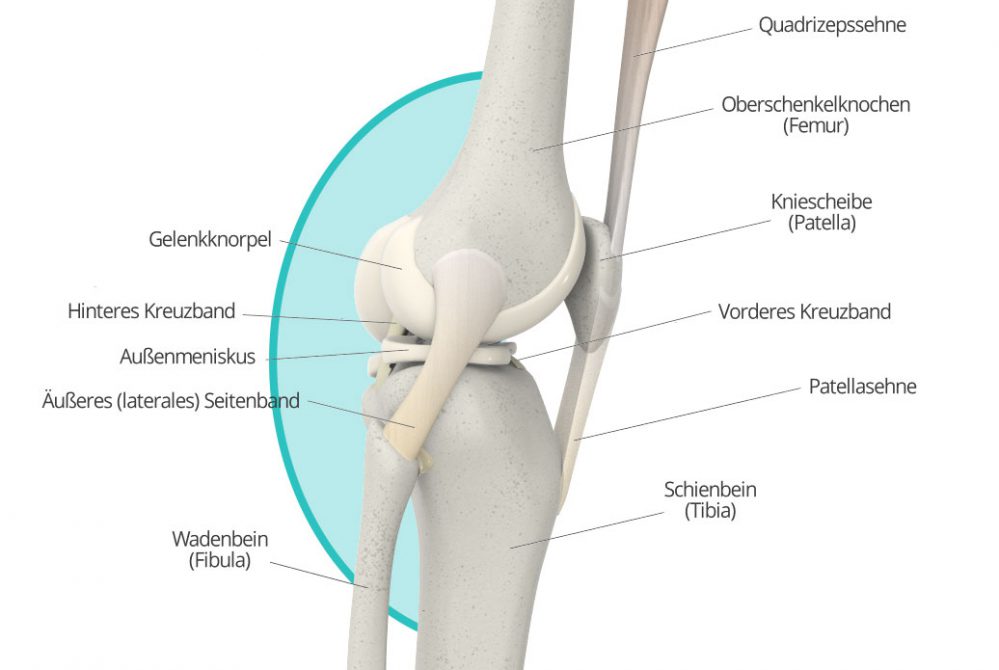

Knieschmerzen, die an der Vorderseite des Knies auftreten, stehen zumeist mit der Patella, (Kniescheibe) in Zusammenhang. Schäden an und Probleme mit der Kniescheibe können diverse Ursachen haben. Wie so oft, kann der Schmerz vielfach auf Überbeanspruchung oder Fehlbelastung – oder Verschleißerscheinungen in deren Folge – zurückgeführt werden. Doch auch Krankheitsbilder wie das Plicasyndrom oder eine so genannte Patellaluxation können Ursachen für Beschwerden vorn am Knie sein.

Manchmal lässt sich der gefühlte Schmerz auch direkt der Kniescheibe zuordnen, zum Beispiel, weil der Schmerz direkt in Zusammenhang mit einer Bewegung der Kniescheibe steht. Im Prinzip kommen hier als Ursache all die Krankheitsbilder in Frage, die auch allgemein bei Schmerzen vorne im Knie mögliche Diagnosen darstellen. Dazu zählen insbesondere das Plicasyndrom, die Patellaluxation sowie Fehl- und Überbelastung und Verschleiß bis hin zur Arthrose. Doch auch etwa ein Bruch der Kniescheibe kommt als Ursache in Frage. Ein Orthopäde kann auch hier die Ursache leicht über eine Anamnese, körperliche Untersuchung sowie in der Regel auch bildgebende Verfahren feststellen.

Achten Sie beim Sport auch auf Zeichen Ihres Körpers, und versuchen Sie, Fehlhaltungen ebenso zu vermeiden wie Überbeanspruchung. Das mindert das Risiko von Sportverletzungen wie Kreuzbandriss oder Meniskusschäden. Sind Ihnen Fehlstellungen wie ein Beckenschiefstand oder eine Fußfehlstellung bekannt, weil diese bereits von einem Arzt diagnostiziert wurden, sollten Sie diese gegebenenfalls korrigieren lassen, um Folgeschäden zu vermeiden.